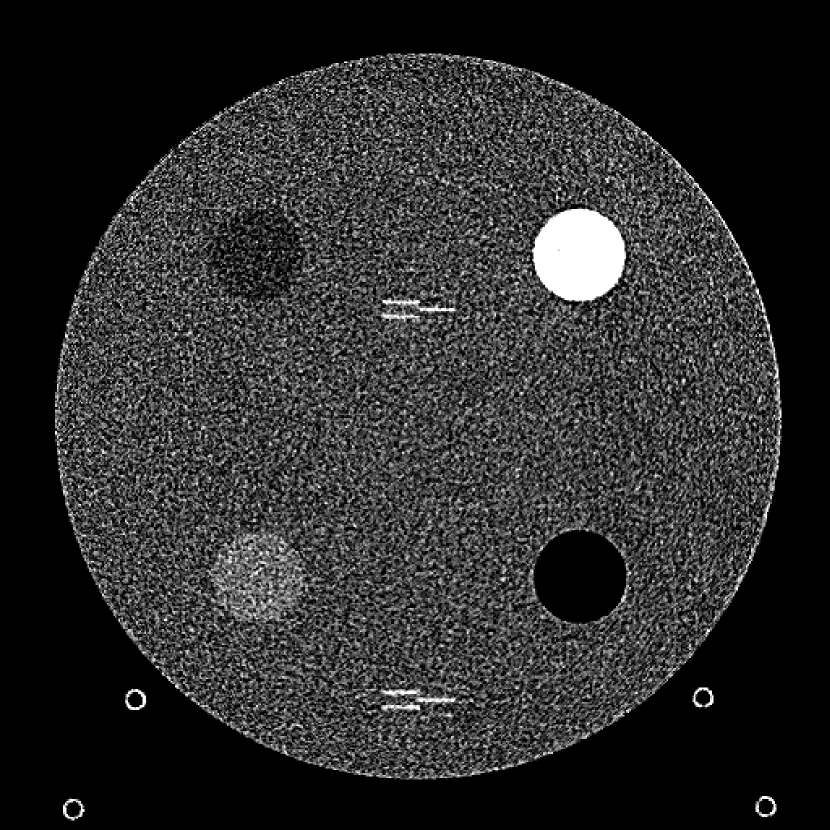

Figure 9: (a) The ACR phantom module 1 with 4 different inserts for CT number fidelity testing. In addition, two ramps of wires are visible near the phantom center. The image display window center is 150 HU and window width is 700 HU. (b) The phantom module 3 with a uniform water-equivalent radiodensity of 0 HU. The display window center is 0 HU and window width is 400 HU.

To evaluate image quality, we first tested the performance of JENG on a standard CT phantom, CT ACR 464 phantom 35. Then we tested JENG on 5 clinical thoracic datasets and 3 abdominal datasets. The ACR 464 phantom contains four modules in total, with each module 40 mm in depth and 200 mm in diameter. The first module has 4 different inserts to test CT number fidelity. In addition, the module contains a series of wires for cross-plane resolution evaluation, shown as white horizontal bars near the center in Fig. 9(a), and are visible in 0.5 mm z-axis increments. The second module tests low contrast resolution, but is not used in this paper. The third module, shown in Fig. 9(b), is a uniform cylinder of water-equivalent material of 0 Hounsfield units (HU), and we used this module to quantitatively measure image noise profile and in-plane resolution. The fourth module consists of resolution bars of various spatial frequencies for analysis on high contrast resolution. To scan the phantom, the scanner setup used dual sources with 2 focal spots at each source. In addition, the projections were acquired using the same protocol for clinical thoracic scans with 100 KV, a nominal tube current of 718 mA and a high helical pitch of 2.8. For all experiments, we compared JENG against the state-of-the-art Siemens ADMIRE, reconstructed with a BL-64 soft tissue sharp kernel, and we define ADMIRE as the clinical standard hybrid IR method for the rest of the paper.

The first experiment we performed was a visual comparison of in-plane spatial resolution between JENG and the clinical standard hybrid IR. We used the ACR phantom module 4 for this evaluation, which has 8 resolution bars of various spatial frequencies from 0.4 mm-1 to 1.2 mm-1. To obtain a fair comparison, we matched the image noise variance in the uniform regions of JENG and the clinical standard hybrid IR and studied their in-plane spatial resolution and undersampling streaking artifacts. In addition, we performed two sets of experiments. The first set of experiments matched their image noise variance at the L1 denoising strength of the clinical standard method with a noise variance of 33926 in the uniform regions. The second set of experiments matched their image noise variance at stronger L3 denoising strength of the clinical standard method with a noise variance of 12988 in the uniform regions.

The resolution bar visual comparison study, however, can be biased by observer subjectivity and may provide little information for spatial resolution beyond a limiting value. Therefore, we also quantitatively evaluated the Task-Based Modulation Transfer Function (MTFtask) of JENG and the clinical standard hybrid IR for a more complete analysis on in-plane resolution, using the edge of the uniform water-equivalent material phantom in module 3 as shown in Fig. 9(b). In summary, our MTFtask analysis was measured with the water-equivalent phantom and averaged all transaxial images in module 3 into a 2D image. Then the MTFtask analysis computed the oversampled edge-spread-function for the generated 2D image, differentiated and Fourier transformed the edge-spread-function to the frequency domain 38, 3. The MTFtask is then the absolute value of the Fourier Transform result and the source code of our MTFtask computations can be downloaded from citation 39.

Fig. 10 is an example image for resolution bars and the spatial frequencies for the bar patterns from top going clockwise are 1.2, 1.0, 0.9, 0.8, 0.7, 0.6, 0.5 and 0.4 mm-1. Fig. 10(a) is the resolution bars reconstructed by the clinical standard hybrid IR at L1 denoising strength. Fig. 10(b) is JENG reconstructed at an image noise variance comparable to the L1 denoising. Fig. 10(c) is the clinical standard hybrid IR at a stronger L3 denoising strength and we can observe that the result at L3 denoising leads to less image noise than the result at L1 denoising in Fig. 10(a). Fig. 10(d) is JENG at an image noise variance comparable to the L3 denoising. To help readers better see the image quality difference between the clinical standard hybrid IR and JENG, Fig. 11 is the difference image between the two algorithms at L1 denoising. A noticeable difference between the clinical standard hybrid IR and JENG is that the clinical standard method in Figs. 10(a) and (c) have strong undersampling aliasing artifacts near the phantom periphery, which show a pattern of high density streakings and the streakings point along the direction of X-rays. In addition, the magnified sub-figures show that the bar pattern at 0.8 cycles/mm is unresolved with blurry details. In contrast, JENG in Figs. 10(b) and (d) effectively decimates the undersampling artifacts and the bar pattern in the magnified sub-figures of JENG is completely resolved with clearer details.